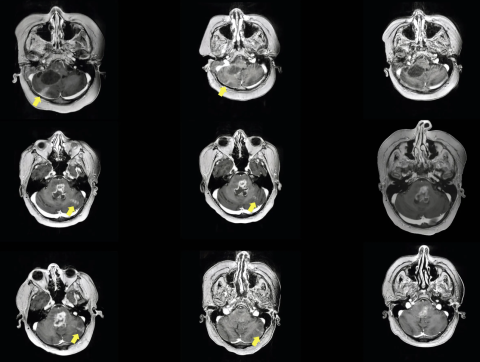

Ultrasound Opens New Front Against Lethal Brain Cancer in Kids Opening the blood-brain barrier may lead to better drug delivery